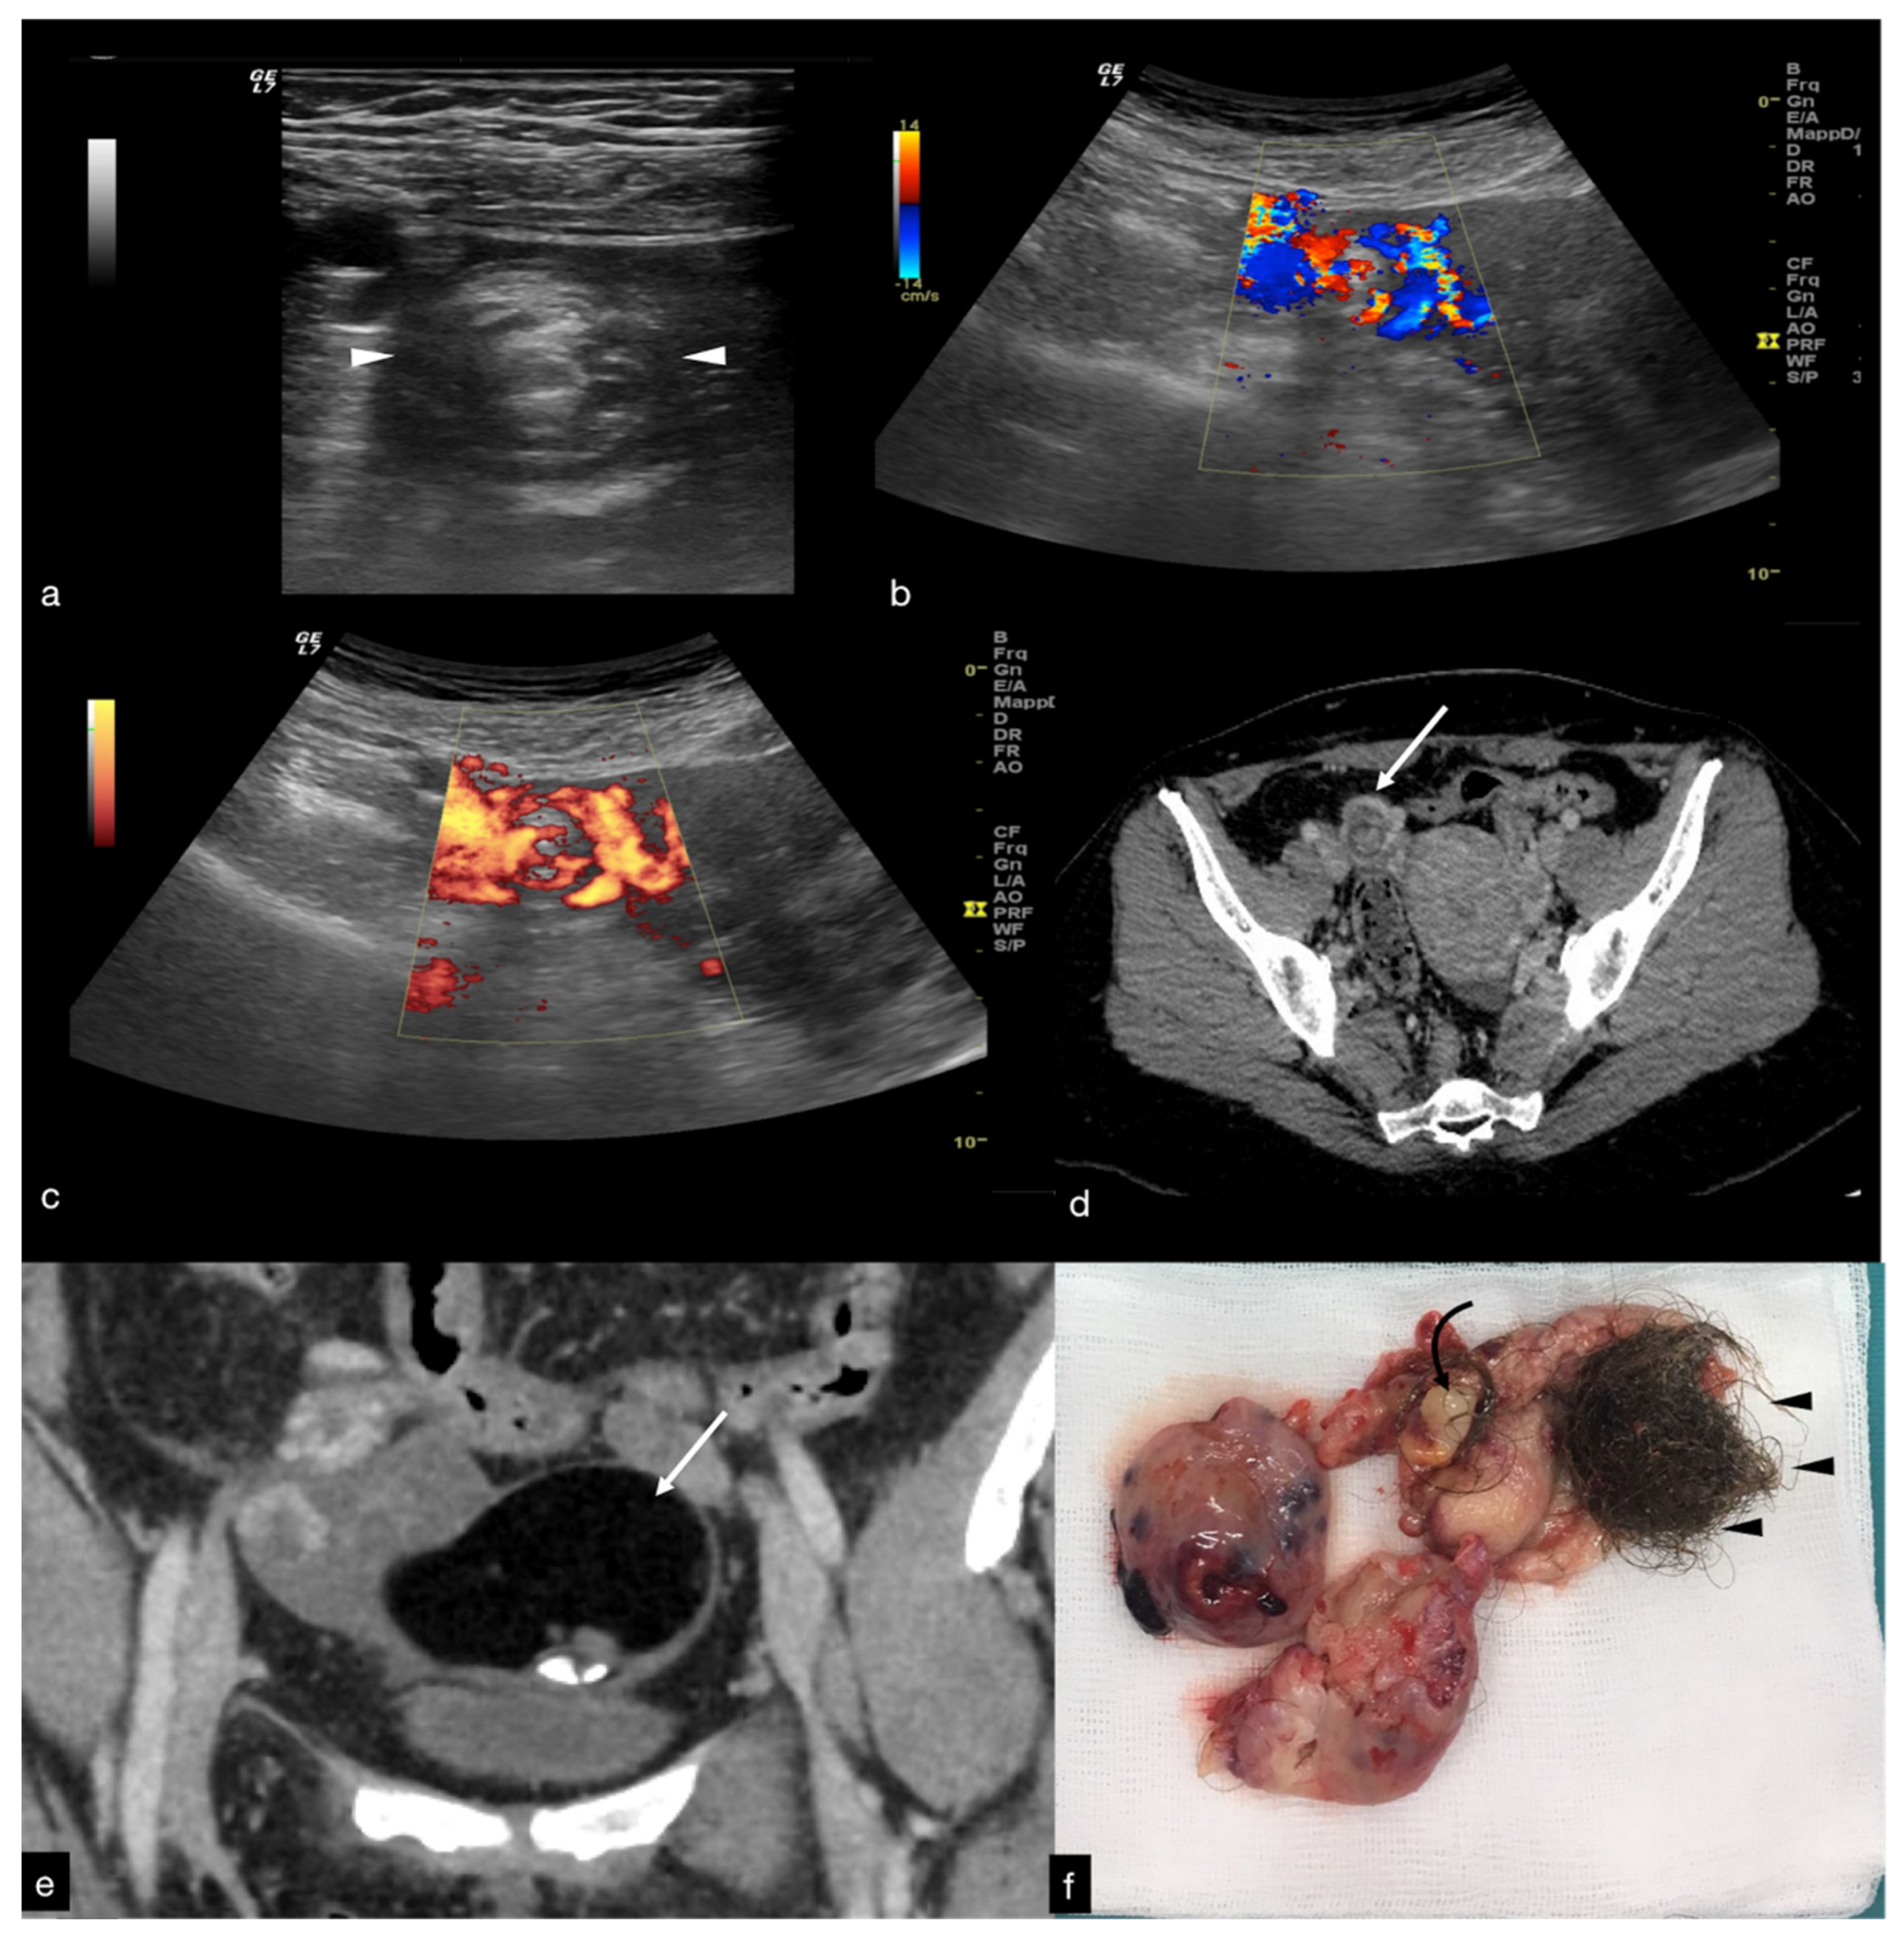

The ovary may be found in an abnormal position, close to the midline of the uterus, higher or lower in the pouch of Douglas, or displaced to the contralateral ovarian space [1,4,5]. The ovarian echotexture shows a hyperechoic central stroma due to the vascular congestion, associated with small peripheral follicles, with a “pearl necklace” appearance and, in the most advanced stages of vascular impairment, a diffusely uneven stroma due to the presence of focal haemorrhages and necrosis. The pathognomonic finding, however, remains the identification of the twisted vascular peduncle (“whirl” sign or “vascular vortex”), obtained by transversal scans along the central axis of the pedicle (Figure 2) [1,2,3,4,5].

The twisted and congested peduncle may appear as an indistinct adnexal mass adjacent to the twisted ovary. The colour Doppler examination allows for the assessment of the degree of torsion, the time elapsed from the beginning of the disease and therefore the degree of vascular compromise [1,2,3,4,5]. Vascular colour Doppler signals in the gonadal tissue are generally absent and this allows for a confident diagnosis with a positive predictive value of 94% (Figure 1).

Diagnostics 12 00939 g001

Figure 2. Same patient of Figure 1. Axial TSA–US image with high frequency probe (a) shows a twisted vascular peduncle (“whirl” sign) from the side of the right adnexal mass of above Figure 1. The twisted adnexal peduncle is better seen at colour-Doppler (b) and power-Doppler evaluation (c) and confirmed also at enhanced CT ((d) arrow), related with the presence of a large mature cystic teratoma ((e) arrow). At the operative specimen, ovarian torsion is confirmed, and the right ovary with the cystic teratoma with its mixed content of hairs ((f) arrowheads) and teeth ((f) curved arrow) is shown. Reprinted with permission from [2].

Figure 16. Thrombosis of the right gonadal vein. TSA–US scan of the left ovarian vein in axial (A) and longitudinal (B) view before delivery show the ovarian vein as a tubular structure with heterogeneous hypoechoic echotexture ((B) arrows), located superiorly to the ovary and anteriorly to the psoas muscle. Contrast-enhanced CT coronal image (C) was performed after delivery and confirmed the left gonadic vein thrombosis (red circle). Reprinted with permission from [46].